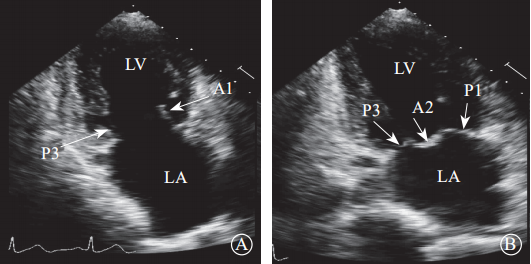

通过采集以下切面显示二尖瓣瓣叶各扇叶。(1)胸骨旁左心室长轴切面,显示A2、P2(图5A);(2)二尖瓣水平短轴切面,显示整个前后叶(图5B);(3)心尖四腔心切面,显示A2、P2(图6A);(4)心尖长轴切面,显示A2、P2(图6B);(5)心尖二腔心切面,显示A1、P3(图7A);(6)心尖二尖瓣交界处长轴切面,显示P1、A2、P3(图7B)。经胸超声心动图通过上述切面评价MR的机制、程度以及部位,并确定瓣膜运动异常的扇叶。

注:LA,左心房;LV,左心室

图 7 经胸二维超声心动图显示二尖瓣瓣叶各扇叶 A. 心尖二腔心切面,显示二尖瓣前叶 A1处、二尖瓣后叶 P3 处;B.二尖瓣交界处长轴切面,显示二尖瓣后叶 P1、前叶 A2、后叶 P3